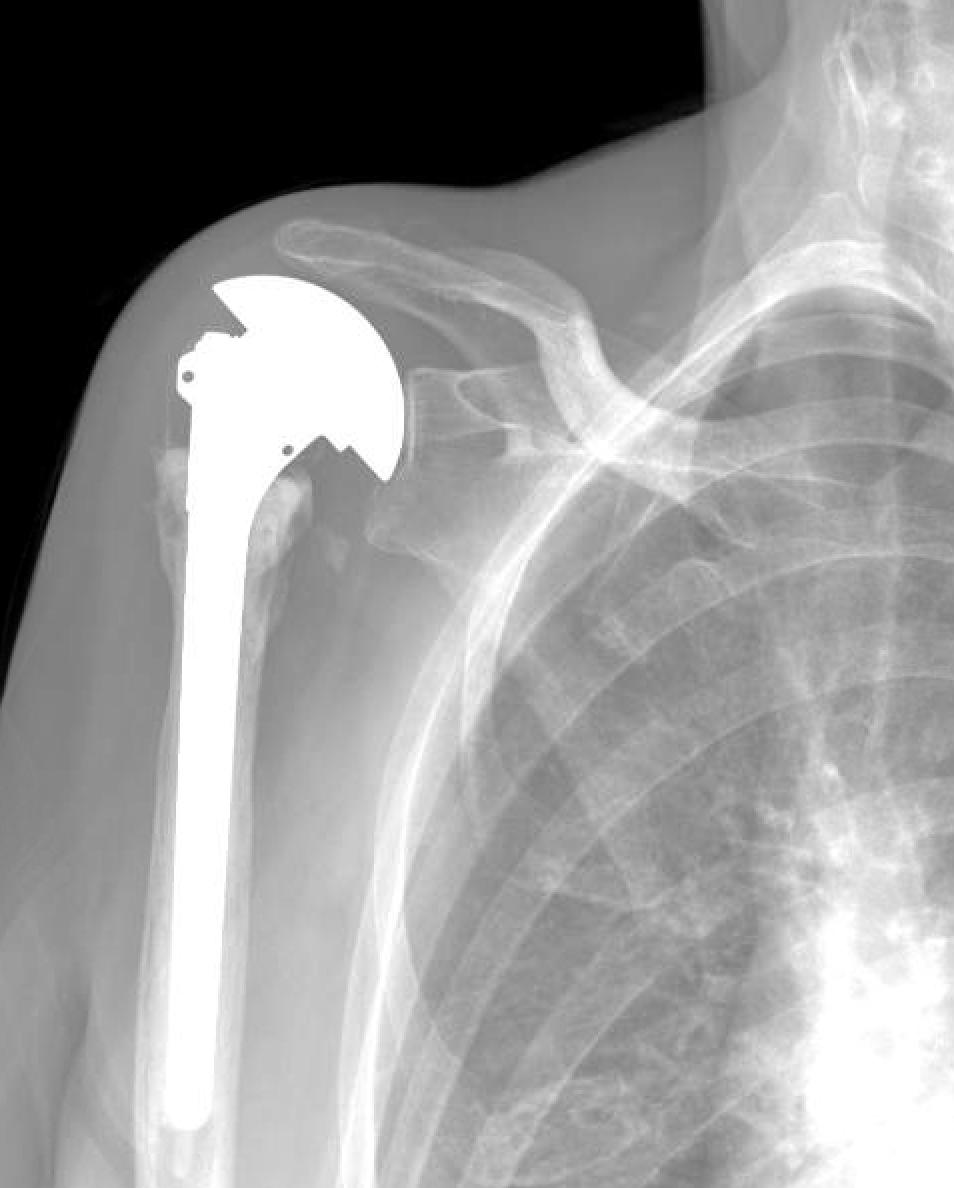

What Happens If Shoulder Replacement Fails . If the artificial shoulder joint wears out or otherwise fails, a surgeon may recommend a. Dislocation, infection, implant loosening from bone, and dissociation. The incidence of failure after shoulder arthroplasty is lower than other major joint reconstructions. When it occurs after surgery to repair a shoulder injury, then it’s considered a failed shoulder stabilization surgery. The most common modes of failure for reverse shoulder replacements are: Reverse total shoulder arthroplasty (rtsa) is a terrific new tool, but failures invariably occur due to infection, instability, baseplate. Revision surgery for shoulder replacement. Revision surgery for total shoulder replacement. If the artificial shoulder joint wears out or otherwise fails, a surgeon may recommend a revision surgery. The results of shoulder joint replacement are often excellent, but failure of shoulder arthroplasty can result because of persistent pain, stiffness, infection, component.

The most common modes of failure for reverse shoulder replacements are: When it occurs after surgery to repair a shoulder injury, then it’s considered a failed shoulder stabilization surgery. If the artificial shoulder joint wears out or otherwise fails, a surgeon may recommend a revision surgery. The results of shoulder joint replacement are often excellent, but failure of shoulder arthroplasty can result because of persistent pain, stiffness, infection, component. Reverse total shoulder arthroplasty (rtsa) is a terrific new tool, but failures invariably occur due to infection, instability, baseplate. Dislocation, infection, implant loosening from bone, and dissociation. The incidence of failure after shoulder arthroplasty is lower than other major joint reconstructions. Revision surgery for total shoulder replacement. If the artificial shoulder joint wears out or otherwise fails, a surgeon may recommend a. Revision surgery for shoulder replacement.

What Happens If Shoulder Replacement Fails If the artificial shoulder joint wears out or otherwise fails, a surgeon may recommend a. Reverse total shoulder arthroplasty (rtsa) is a terrific new tool, but failures invariably occur due to infection, instability, baseplate. The incidence of failure after shoulder arthroplasty is lower than other major joint reconstructions. The results of shoulder joint replacement are often excellent, but failure of shoulder arthroplasty can result because of persistent pain, stiffness, infection, component. Dislocation, infection, implant loosening from bone, and dissociation. When it occurs after surgery to repair a shoulder injury, then it’s considered a failed shoulder stabilization surgery. If the artificial shoulder joint wears out or otherwise fails, a surgeon may recommend a. If the artificial shoulder joint wears out or otherwise fails, a surgeon may recommend a revision surgery. Revision surgery for shoulder replacement. Revision surgery for total shoulder replacement. The most common modes of failure for reverse shoulder replacements are: